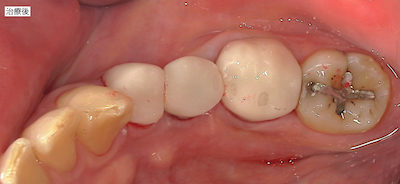

治療前後の比較です。

患者さんはとても喜んで下さったので良かったです。